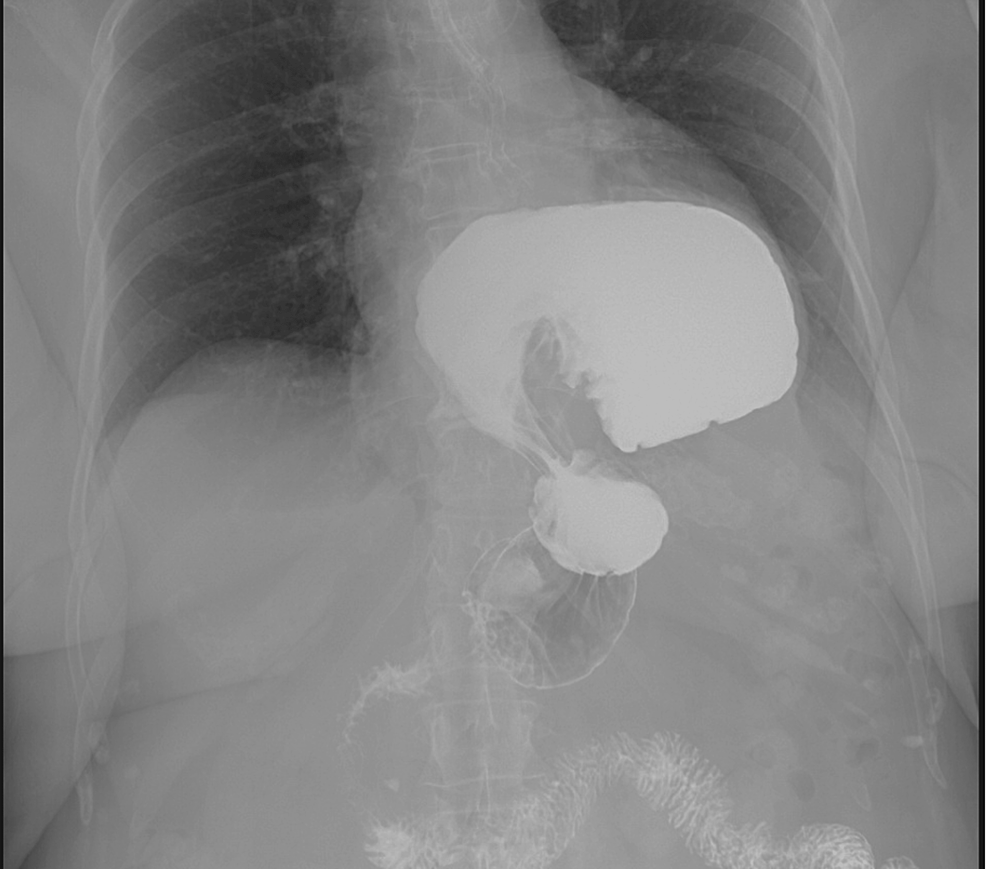

x ray of volvulus gastric Radiology Imaging Gastric Volvulus Radiographics Abdominal pain, nausea, and vomiting are common presenting symptoms among adult patients seeking care in the. It can be both an emergency and a chronic intermittent. Gastric rotation and volvulus may occur in an organoaxial plane (along the long axis of the stomach) or in the mesenteroaxial plane. Gastric volvulus is a rare entity with a spectrum of acute and. Gastric Volvulus Radiographics.